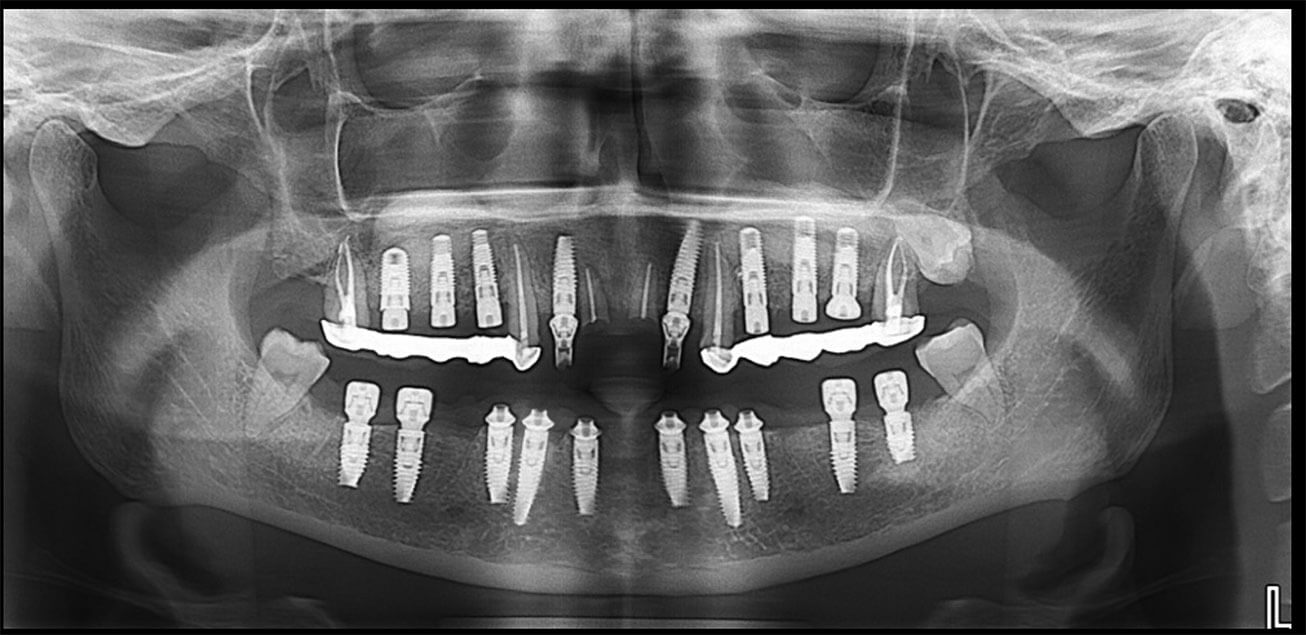

Medicii implantologi din clinica noastră au toate specializarile necesare și o experiență de peste 25 de ani în implantologia dentară tratând cu succes cele mai complicate cazuri de augmentari osoase, sinus lift extern și intern. (+radiografii augmentare osoasă majora)

Pacientul se prezintă în cadrul clinicii noastre. În urma efectuării investigațiilor radiologice (radiografie panoramică și CBCT) se primește un plan de tratament care va cuprinde toate costurile necesare. Dacă pacientul acceptă planul de tratament, următoarele programări se vor face cât mai repede posibil.

Înainte de a fi inserat implantul, fiecare caz în parte este extrem de bine planificat în funcție de necesitățile fiecărui pacient. Există situații în care inserarea implantului se face cu ajutorul chirurgiei ghidate. Acest lucru presupune că ghidul respectiv care se pune în gura pacientului în timpul intervenției este planificat de către chirurg împreună cu tehnicianul dentar. Chirurgia ghidată este mult mai precisă și mai sigură.

Există diferențe între tipurile de implant, atât din punct de vedere calitativ, cât și de design. Unele alegeri le puteți face chiar dumneavoastră, altele țin de competența medicului. În cadrul clinicii noastre se lucrează cu următoarele tipuri de implanturi: implant premium Straumann, implant Zimmer trabecular metal, implant Bredent, implant REX, implant MIS, implant iRES.